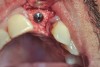

Fig 12. (Case 2) Tooth No. 9 was extracted; the buccal plate was dehisced.

Figure 12

Fig 13. Flap elevated 6 months after d-PTFE barrier and bone graft were placed; the barrier was removed after 4 weeks. This photograph shows the buccal plate regenerated.

Figure 13

Fig 14. An implant was inserted in regenerated bone.

Figure 14